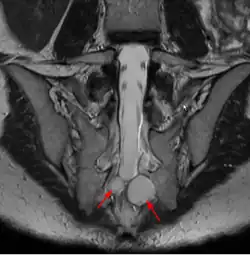

| MRI image showing a Tarlov cyst | |

Tarlov cysts are most commonly located in the S1 to S4/S5 region of the spinal canal, but can be found along any region of the spine. Tarlov cysts typically form on the extradural portions of the sacral nerve roots, most often near the dorsal root ganglion of the dorsal (sensory) nerve roots. They arise within the perineural space, between the endoneurium and perineurium. Occasionally, these cysts are observed in the lumbar and thoracic spine.[19] The cysts are often multiple, extending around the circumference of the nerve, and can enlarge over time to compress neighboring nerve roots, to cause bone erosion.[22]

MRI

MRI, or Magnetic Resonance Imaging, is considered the imaging study of choice in identifying Tarlov cysts. MRI provides better resolution of tissue density, absence of bone interference, multiplanar capabilities, and is noninvasive. Plain films may show bony erosion of the spinal canal or of the sacral foramina. On MRI pictures, the signal is the same as the CSF one.